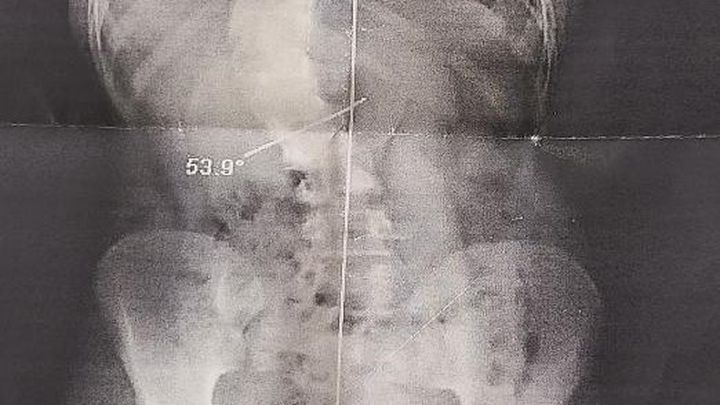

Yep, that's Mazie's spine! But it will look much better in October!!!

Unfortunately Mazie has been diagnosed with severe double scoliosis (curvature of the spine in two places) and kyphosis (excessive outward curvature of the spine) and her doctors have attempted everything possible to help to straighten her back including braces and physical therapy. Despite their best efforts, her condition has worsened and she has to have spinal fusion surgery followed by an extensive recovery period.